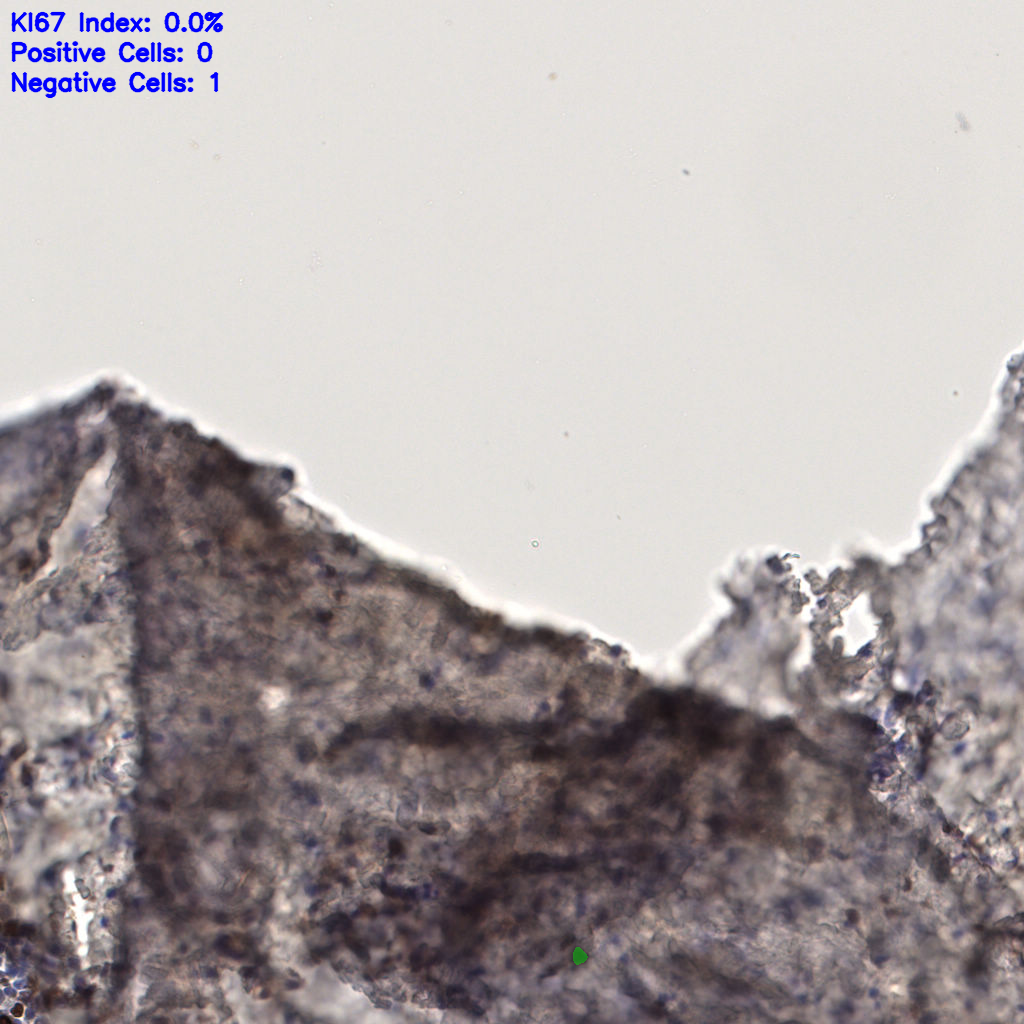

7.85%

Ki67 指数

阴 1104

阳 94

切片统计

总切片

1953

有效

288

已标记

有效率

15%

标记后

标记前